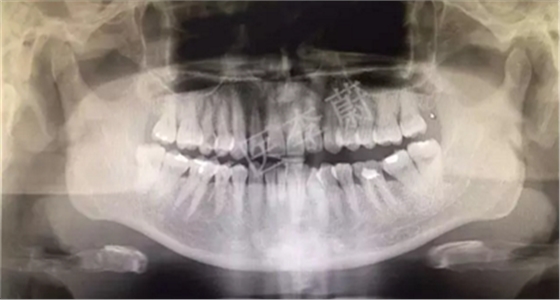

曲面斷層片

X片示:15殘冠影,根尖有骨密度降低影。